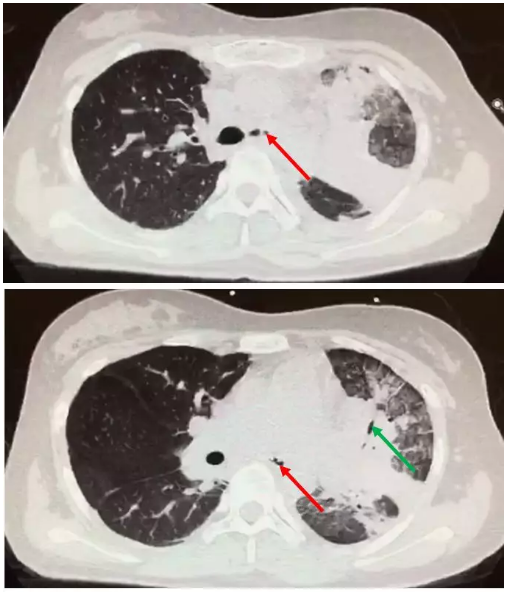

"致命霉栓"(1)---阻塞性支气管毛霉病 - 好大夫在线

图片尺寸507x592